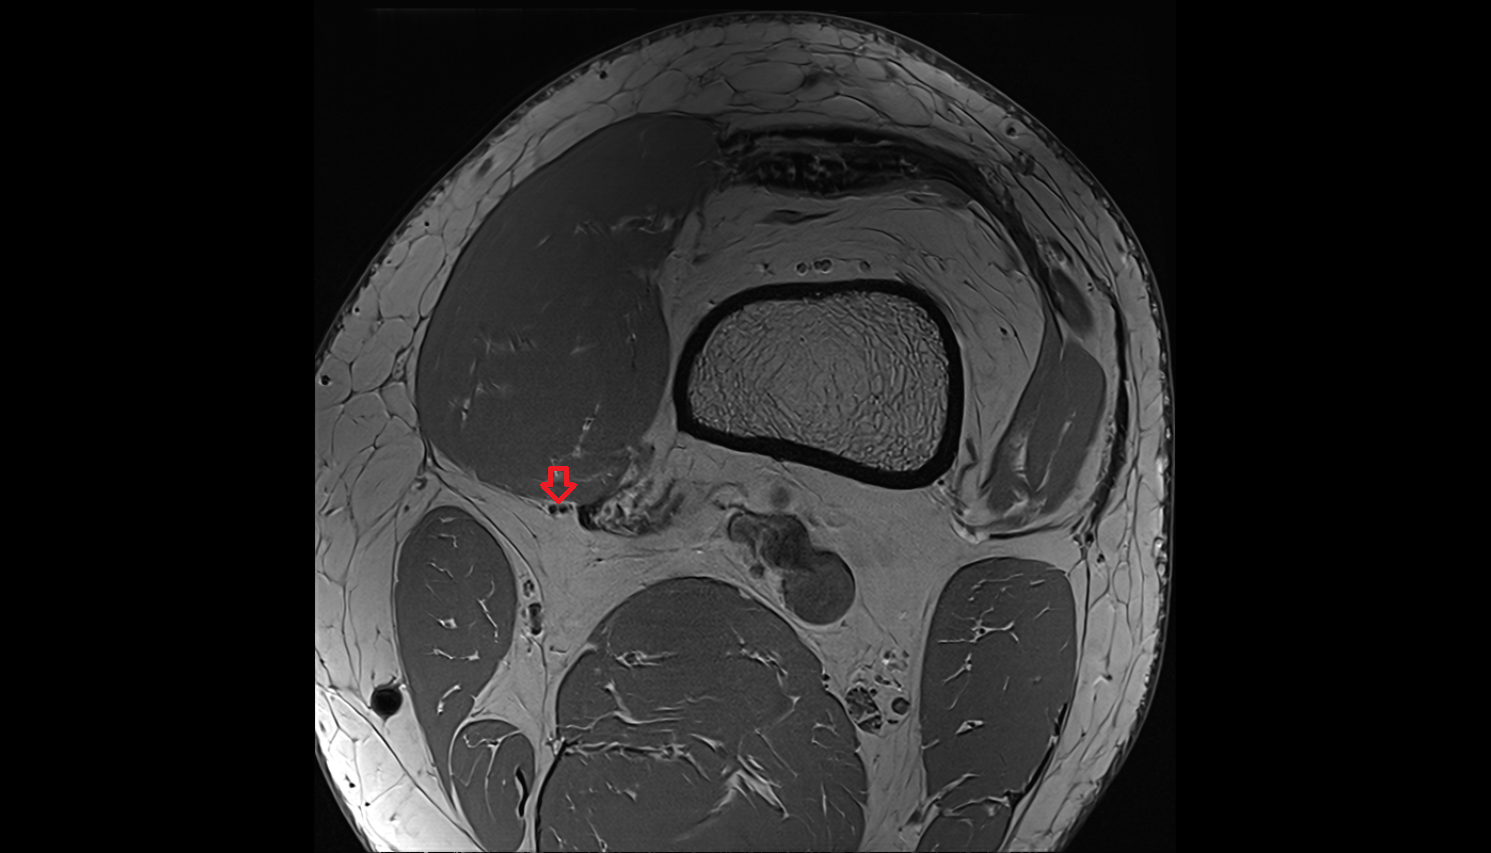

- Anterior cruciate ligament

- Posterior cruciate ligament

- Knee Joint